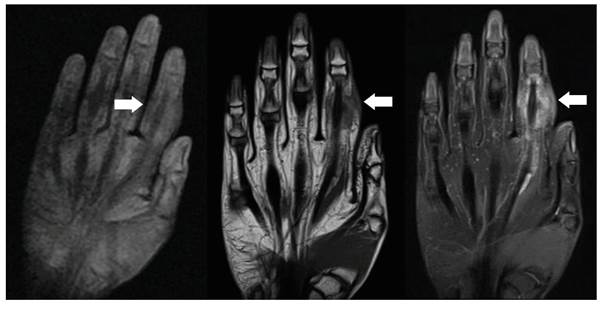

Durante la estancia en el hospital se realizaron análisis complementarios, siendo los resultados: leucocitos de 11 060 /µl, hemoglobina de 11 gr/dl, eosinófilos 1,9%, linfocitos 6,9%, proteína C reactiva 7,72 mg/dl, velocidad de sedimentación globular 67 mm/hora, deshidrogenasa láctica 279 U/l, fosfatasa alcalina 133 U/l y una prueba ELISA para VIH de cuarta generación no reactivo. De esta manera, dentro de los diagnósticos diferenciales se planteó un probable proceso neoformativo secundario a distancia, solicitándose una tomografía que incluyó los segmentos corporales de cabeza, tórax, abdomen y pelvis. Este estudio reportó “a nivel cerebral un quiste aracnoideo de 49 x 35 mm en el área temporal anterior izquierdo, una lesión pleuroparenquimal pulmonar de aspecto secuelar con escasa efusión pleural izquierda, adenopatías mediastinales reactivas, un área hipodensa de 34 x 29 mm en la región anterior periférica y una lesión osteolítica en cuerpo vertebral de D9” (figura 2). Asimismo, se amplió los estudios del dedo comprometido con una ecografía Doppler de la mano derecha que reportó una “lesión expansiva vascularizada en falange proximal del segundo dedo con compromiso óseo”. La resonancia magnética nuclear de dicho dedo evidenció una “lesión expansiva de 57 x 22 x 17,3 mm con fractura patológica en tercio medio diafisario de falange proximal de segundo dedo, con rebordes lobulados y efecto de masa desplazando el tendón flexor hacia palmar. Se observó también compromiso de articulación interfalángica proximal, y de la base de falange media. Tras la administración de contraste muestra ávido realce” (figura 3). Durante la hospitalización, los controles de BK de esputo, posterior a un mes de tratamiento con el esquema sensible, fue paucibacilar (8 BARR/100 campos).

Figura 3 Resonancia magnética nuclear de mano derecha con contraste muestra lesión expansiva a nivel de segundo dedo de mano derecha